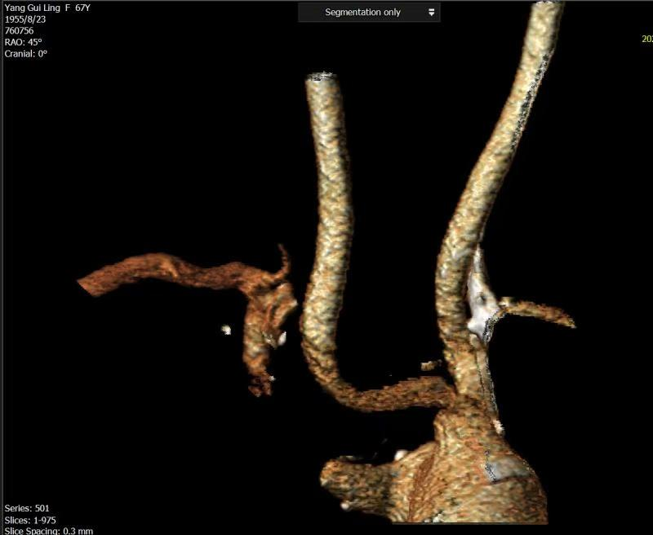

病例二

复杂的右锁骨下动脉闭塞病变:

对于闭塞病变,开通导丝的方向至关重要。根据CTA提示的特定角度(如 RAO 32° CRA 12°)进行投照,能为术者提供最清晰的路径导向,成功引导导丝通过闭塞段。

图:CTA提示 RAO 32  CRA 12

图:按RAO 32  CRA 12开通成功